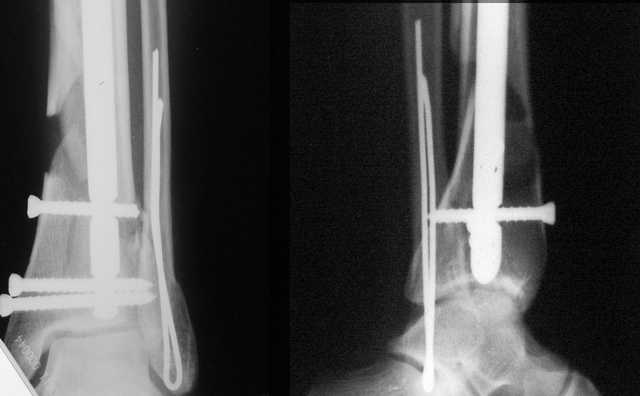

A propos fibular fixation if one is eager to stabilize it separately. In the fracture pattern a way of closed fixation by V-shaped stressed wire (advanced by colleagues from Moscow, prof. Lazarev A.F. et al.) must be excellent. We use indirect closed reduction by the external fixator. Example attached, that fibular fracture is even more suitable for plating but the wire did the job.

I didn't perform stress tests, at least it prevents fibula against secondary displacement. Stressed 2 mm double wire is not so weak.

I used it only in two fibular cases recently. Colleagues from Moscow use the wires mostly for proximal humerus and even femoral neck.